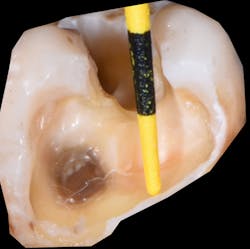

Figure 2: Curing lights can only penetrate a few millimeters before the intensity drops off quickly.

Historically, composite resins have been classified primarily based on the particle size in the filler: macrofill, microfill, hybrid, microhybrid, nanofill, and nanohybrid. And, depending on the amount of filler load, there are the standard “packable” or normal viscosity resin and flowable resins that are more fluid in nature. Typically, when placing resin into a cavity preparation, especially in Class I and Class II preparations, careful attention is needed in the overall placement, as many of these preparations can be several millimeters in depth (figure 1) and too deep for sufficient penetration of light (figure 2) and proper curing of the resin.